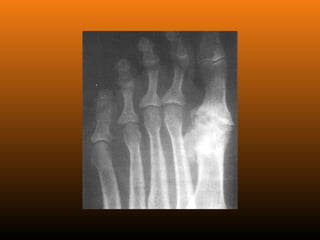

RADIOLOGIA

No início da doença não se observam anormalidades. Com seu

desenvolvimento, observam-se:

 Diminuição do espaço intra-articular

 Esclerose subcondral (eburnação)

 Osteófitos;

 Erosão e anquilose óssea (pseudocistos ósseos).